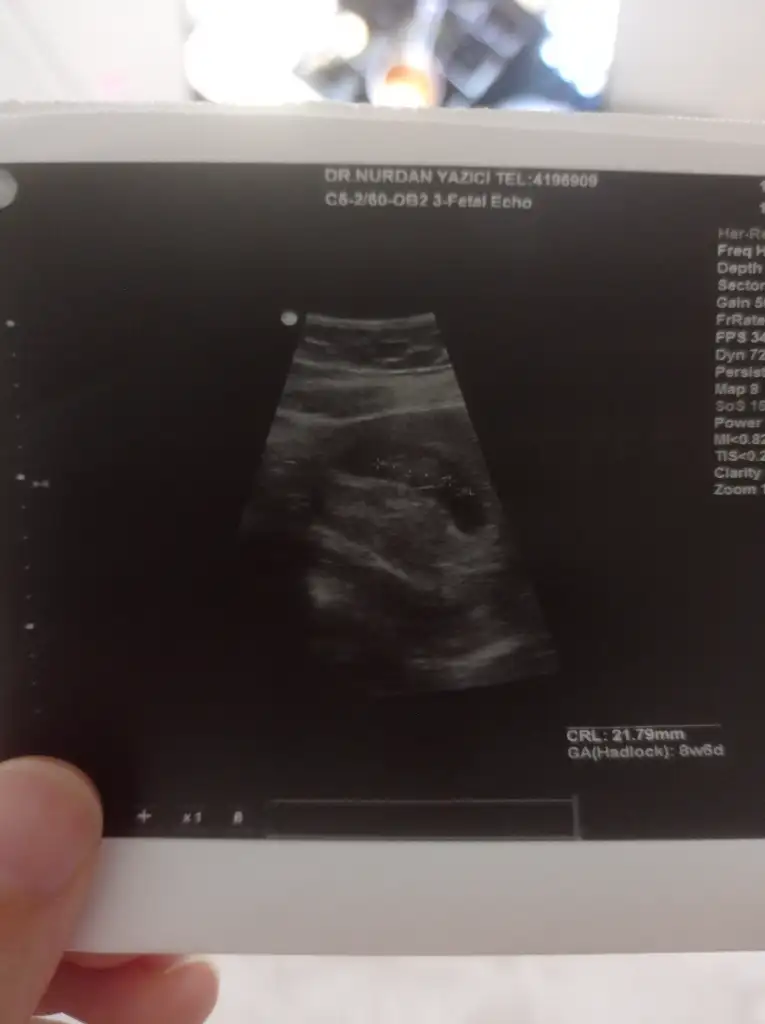

8+3 karından ultrasonla çekildi cinsiyet tahmini yapabilecek var mı

8+6 karından ultrasonla çekildi cinsiyet tahmini yapabilecek var mı acaba çok merak ediyorum